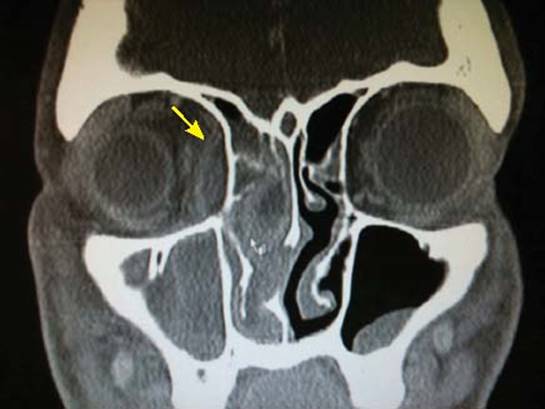

An SPA should be suspected when a patient who has orbital cellulitis develops worsening proptosis and gaze restriction. It can also be the presenting symptom. Ophthalmologic evaluation is essential if an SPA is suspected. A loss of red− green perception may happen before the deterioration of visual acuity. A contrast-enhanced sinus CT is required to verify the diagnosis and to assess its severity. Findings are a ring-enhanced lesion or air–fluid level in the extraconal space, displacement and enlargement of the medial rectus muscle and proptosis (Figs. 8.3 and 8.4).

Figure 8.3 Computed tomography axial scan of ethmoiditis with right side subperiosteal abscess (arrow).

Figure 8.4 Computed tomography scan (coronal view) showing lateralization of the right globe due to subperiosteal abscess (arrow).